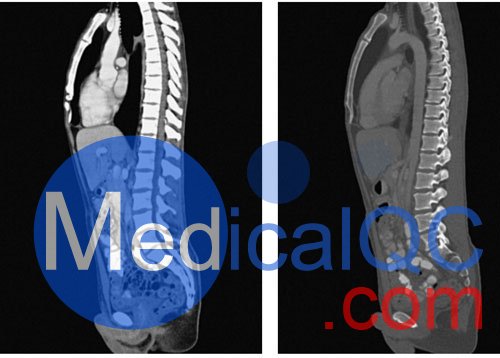

WEK57-01門靜脈期軀干模體,WEK57-01軀干模型模擬了門靜脈期的造影劑增強(qiáng)胸部、腹部和骨盆。它覆蓋了會陰的第二胸椎。

右側(cè)有髂淋巴結(jié)腫塊。

該模型可用于 CT(包括 CBCT)以評估和優(yōu)化成像性能和后處理應(yīng)用,包括支持 AI 的應(yīng)用。它也適用于培訓(xùn)目的。

該模型提供了對軟組織和骨組織的詳細(xì)而逼真的模擬。包括肺在內(nèi)的空隙充滿了大約 -160HU的纖維素聚合物復(fù)合材料。

真實模擬脈管系統(tǒng)、骨骼和軟組織,包括肺、心臟、肝臟、膽囊、胰腺、脾臟、腎上腺、腎臟、胃、小腸、結(jié)腸、膀胱和前列腺。

右側(cè)髂外淋巴結(jié)腫塊。

大?。?約 267 x 185 x 466 mm

重量: 約 11040 g

基材: 纖維素-聚合物復(fù)合材料

最佳管電壓: 120 kVp – 可根據(jù)要求進(jìn)行調(diào)整

WEK57-01門靜脈期軀干模體,WEK57-01軀干模型成像效果圖:

SAG: